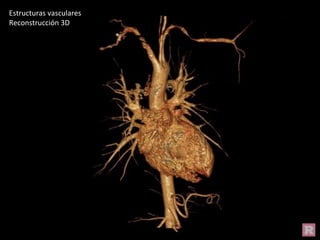

Reconstrucción 3D

Estructuras vasculares